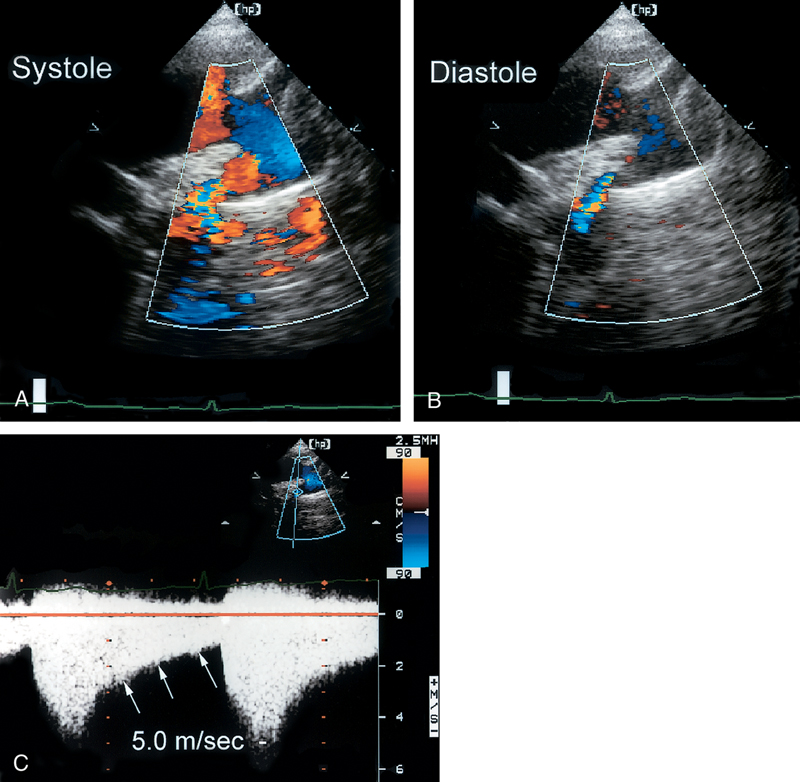

فحوصات تشخيصية لبعض امراض القلب والشرايين التاجية